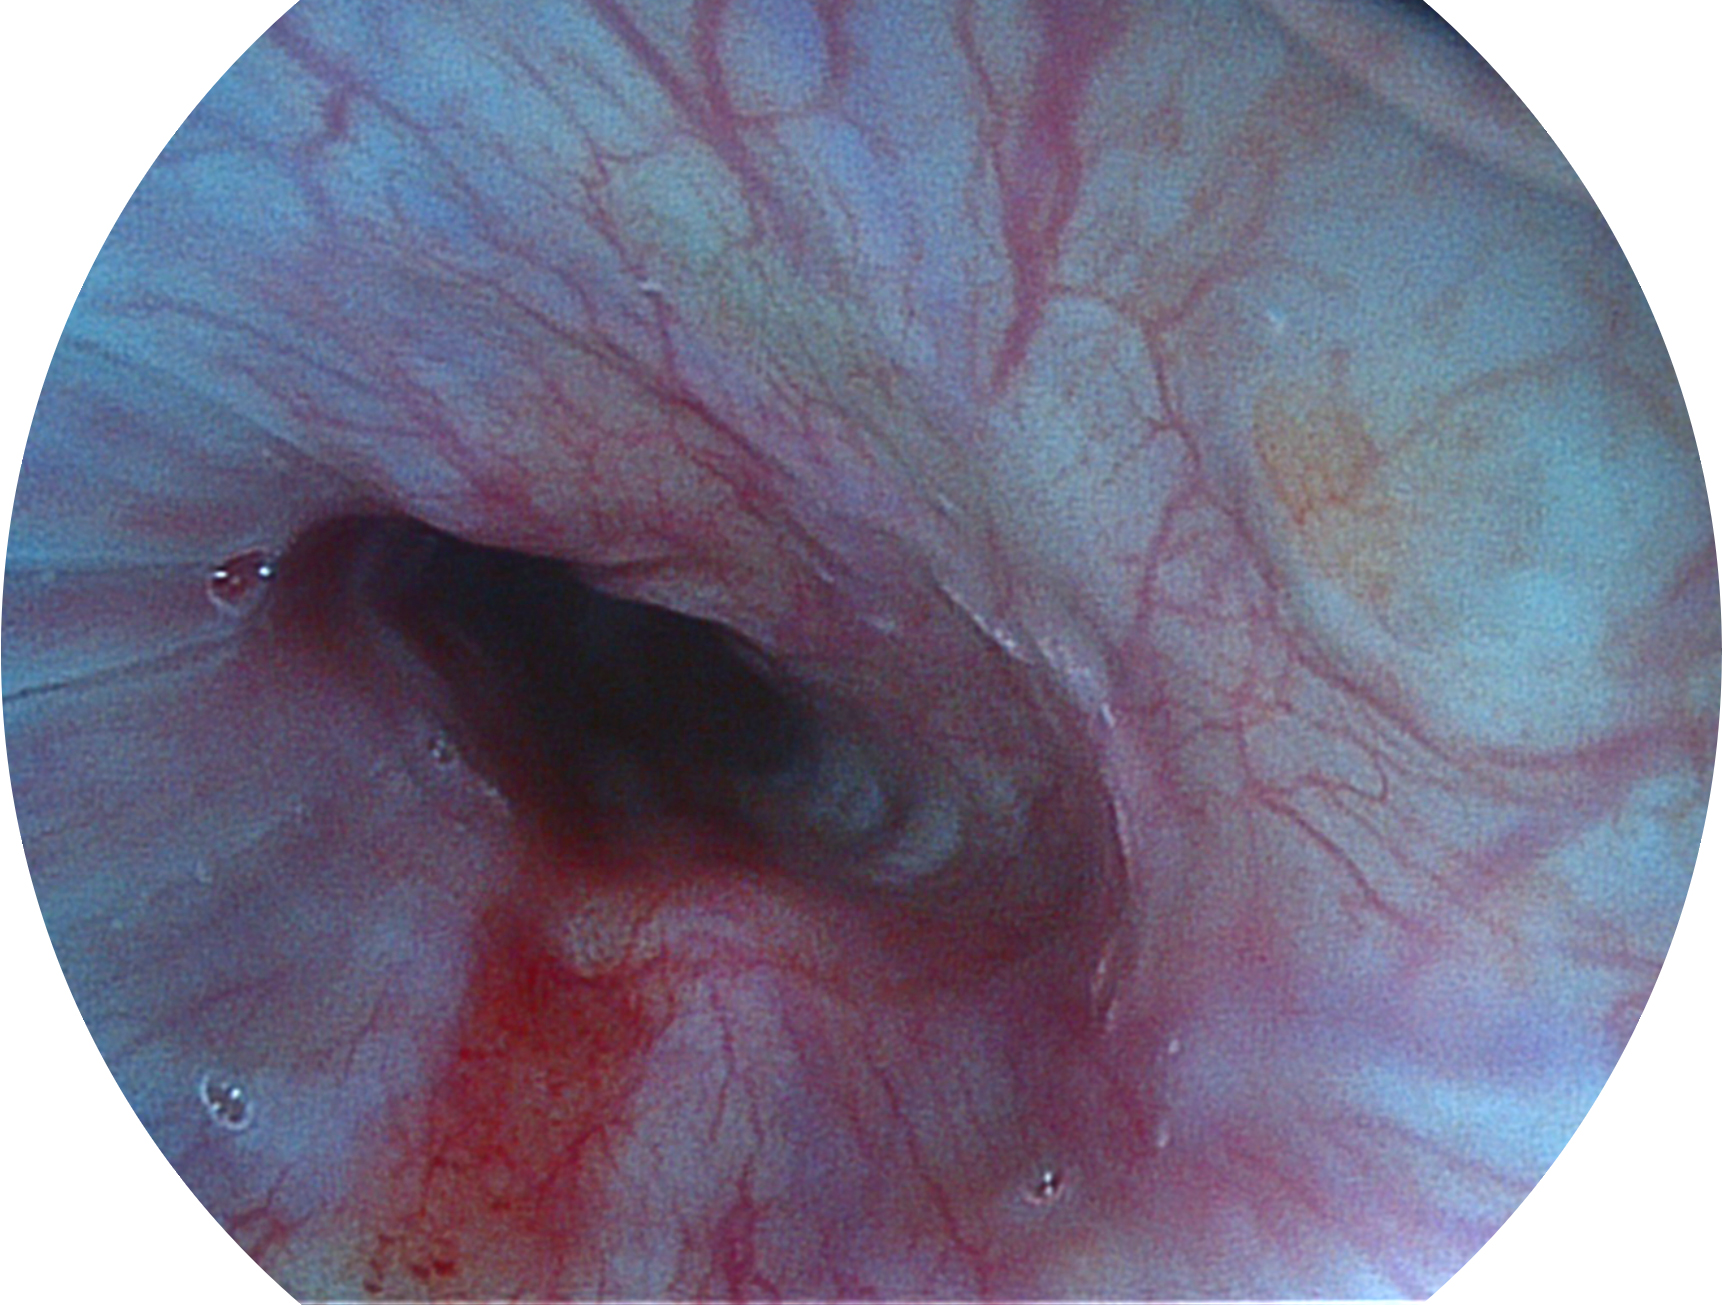

与上一代VIST相比,摒弃了滤光转轮而直接采用光谱组合的方案,加入了血红蛋白吸收高峰与次高峰的蓝紫光和绿光光谱,更有利于黏膜血管吸收,突显浅表层血管和中层血管的对比度,因而具备更高的图像对比度,近景观察时,有助于微细结构变化及病灶边界的观察。

• 白光图像 VIST图像